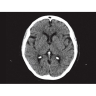

Позволяет проводить комплексные исследования всех анатомических зон, включая нейровизуализацию, ангиографию, исследования органов грудной и брюшной полости. Особенно эффективен для раннего выявления онкологических заболеваний.

Обеспечивает высокую точность при кардиологических исследованиях, визуализации костных структур и суставов. Подходит для динамического наблюдения в ходе лечения.